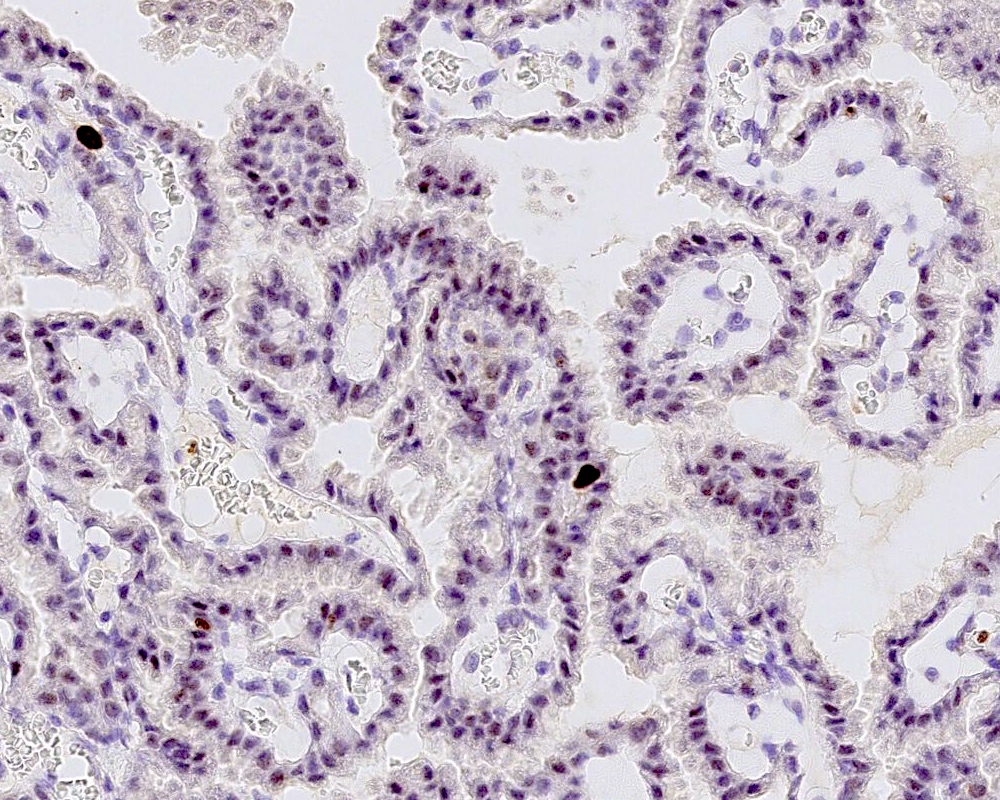

Positive stains

- Transthyretin, KIR7.1, EAAT1, S100, pancytokeratin (cytokeratin, MNF116, AE1 / AE3), CK7 > CK20

- Can be positive for GFAP, synaptophysin, S100

- Ki67 / MIB1 proliferation index may be used for grading (variable and subjective interpretation)

- Choroid plexus carcinoma: p53 variable, SMARCB1 / INI1 and SMARCA4 retained nuclear expression

- References: Neurosurgery 1988;23:384, Acta Neuropathol 1990;80:635, Am J Surg Pathol 2006;30:66, J Neuropathol Exp Neurol 1999;58:398

Microscopic (histologic) images